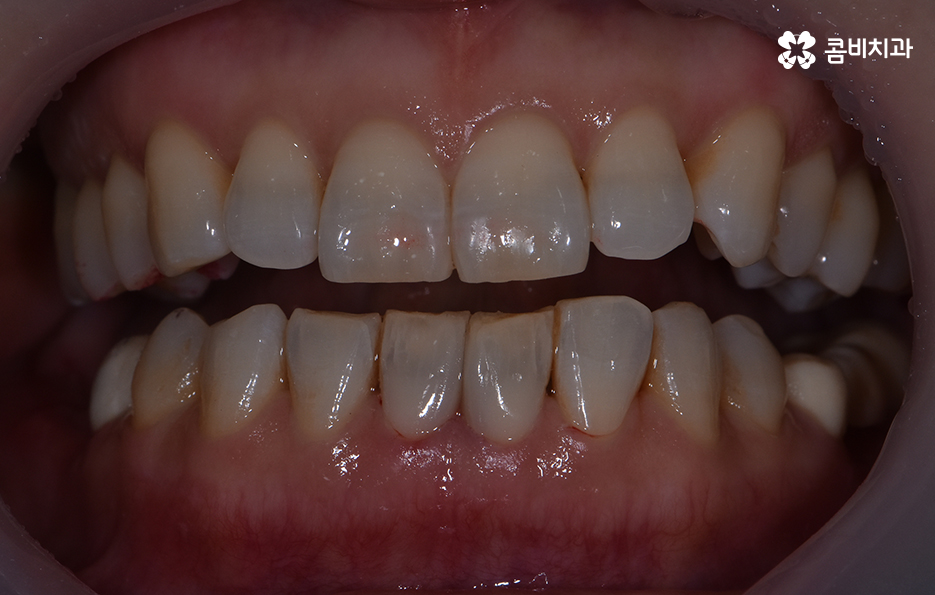

위 환자분의 경우 블랙트라이앵글 레진으로 치료를 하였는데

이러한 레진 치료의 장점은 빠르게 심미성을

회복할 수 있다는 점이며 비교적 저렴하다는 장점이 있습니다.

블랙트라이앵글은 레진을 통해서 치료도 가능하지만

레진은 간단한 반면에 떨어지거나 변색이 발생할 수 있으며

잇몸 염증을 유발하게 되는 경우도 있습니다.